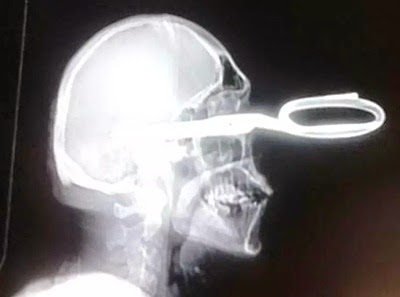

Um homem assustou os médicos de um hospital na cidade de Chihuahua, no noroeste do México, quando chegou na recepção e disse: "Eu tenho um probleminha. Será que alguém pode me ajudar?". Ele estava com parte de uma tesoura fincada em sua cabeça. As informações são do Daily Mail. Segundo a publicação, Jonas Acevedo Monroy, 32 anos, foi apelidado de "O cavalheiro" pelos funcionários do hospital, devido a sua educação em meio à situação em que se encontrava. De acordo com a reportagem, ele estava em seu bar, quando um homem violento começou a perturbá-lo. Monroy teria oferecido um drink para acalmar o homem. O agressor não aceitou a bebida, tirou parte de uma tesoura de seu casaco e fincou na cabeça do dono do bar. Monroy pegou uma carona com um de seus amigos e foi para o hospital. Ele estava sangrando muito quando chegou na recepção do hospital e pediu "educadamente por ajuda". Os médicos afirmam que ele teve sorte de não morrer. A tesoura atingiu nervos e veias de seu rosto, mas as lesões não são fatais. Apesar da gravidade de seus ferimentos, a vítima fez uma recuperação completa e já está em casa. (Terra)